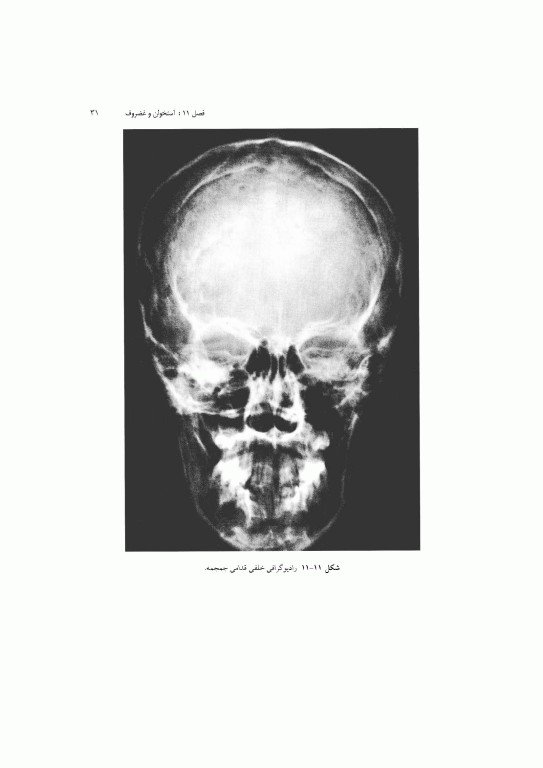

1. آناتومی بالینی: پایه این بخش اطلاعات پایه سودمندی را برای کمک به پزشک در تشخیص و طراحی درمان ارائه مینماید. نمونه‌های متعدد رادیو گرافهای نرمال، CT اسکن، MRI و سونوگرامهای مربوطه نیز نشان داده شده است. همچنین، تصاویری از آناتومی مقطع عرضی آورده شده است تا دانشجو با تجسم آناتومی سه بعدی آشنا شود که این امر در تفسیر کلیشه‌ها بسیار مهم است.